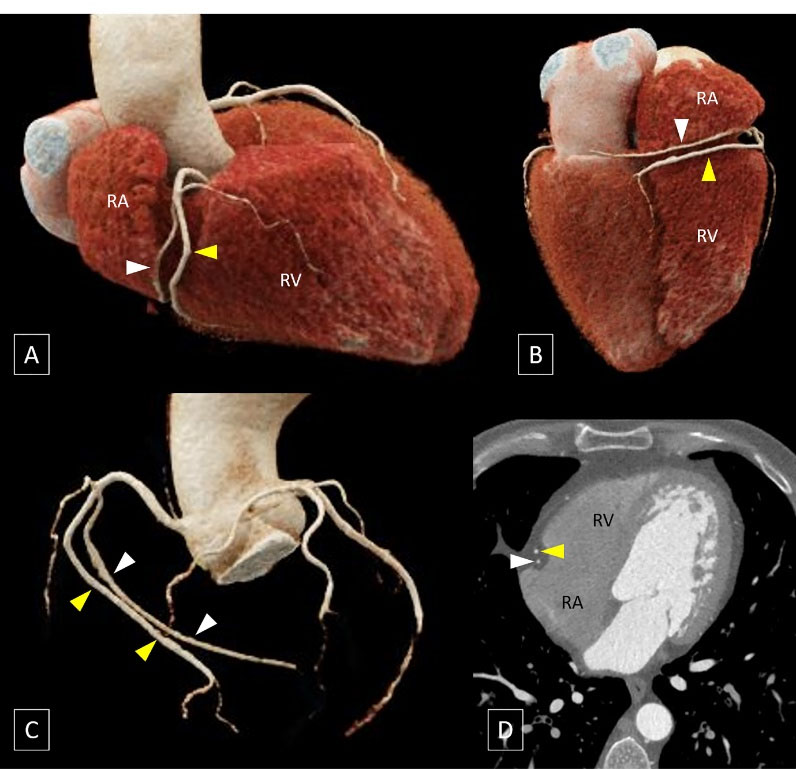

To the best of our knowledge, the variant encountered in the present case has not been reported previously and is analogous to the widely recognized “dual left anterior descending artery (LAD)” where a short LAD terminates in the proximal part of the anterior interventricular groove and a long LAD, that initially courses outside the anterior interventricular groove, re-enters the anterior interventricular groove in its distal part (Figure 2).1 However, in the context of RCA, the term “dual RCA” has traditionally been used to describe the presence of either two parallel RCA arising from separate ostia or two parallel branches of similar calibre arising from a single proximal RCA proper and running in the right AV groove with both branches reaching the crux cordis (Figure 3).2 The term “dual RCA” has also been used interchangeably with “duplicated RCA” or “double RCA”.

Volume rendered images (A to C) show a short left anterior descending artery (LAD, white arrowhead) which terminates in the proximal part of the anterior interventricular groove (indicated by asterisks) and a long LAD (yellow arrowheads), that initially courses outside the anterior interventricular groove on the left ventricular (LV) side and re-enters the groove in its distal part. [RV: right ventricle]

Volume rendered images (A to C) and oblique coronal image (D) showsthe presence of two parallel branches (indicated by white and yellow arrowheads) of similar calibre arising from a single proximal RCA proper and running in the right AV groove with both branches reaching the crux of heart. [RA: right atrium; RV: right ventricle]